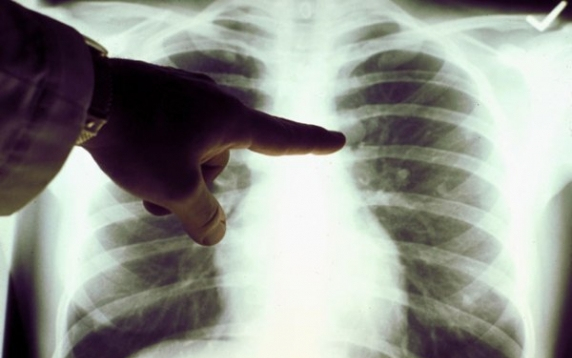

A tuberkolózis eredete hetvenezer évvel ezelőtti vadászó-gyűjtögető életmódot folytató afrikaiakhoz köthető – állapította meg egy tanulmány, amelyről a BBC számol be. A kutatás ellentmond annak az általános meggyőződésnek, hogy a tbc tízezer évvel ezelőtt, állatokról terjedt át emberre.

Korábbi tanulmányok azt találták, hogy a tbc tízezer évvel ezelőtt alakult ki Afrikában a neolitikum demográfiai átalakulása során, amikor emberek lepték el a kontinenst és a mezőgazdaság lett a meghatározó tevékenység.

A kutatás keretében a szakemberek 259 tbc törzs földrajzi és genetikai adatait gyűjtötték össze, s megerősítették az a hipotézist, hogy a tbc eredetileg emberekből indult ki, ráadásul hatvanezer évvel korábbról származik, mint azt eredetileg gondolták.

Amikor az emberi populáció elkezdett terjeszkedni, a tbc is aktívvá vált és képes volt a szaporodásra. A kutatás következő fázisában genetikai információk felhasználásával szeretnék megállapítani, hogy mi a folyamata a tbc aktiválásának, illetve inaktiválásának.

A tbc még mindig globális veszély, ami 2011-ben 1,4 millió ember halálát okozta.